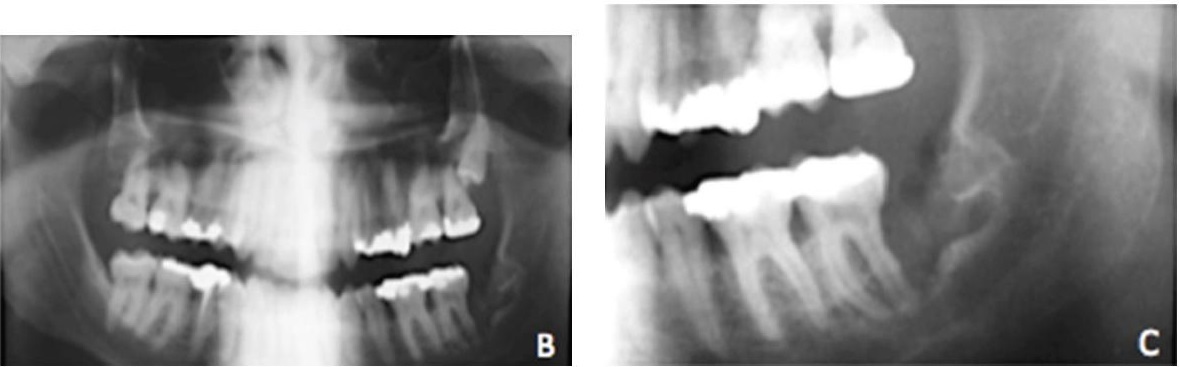

Киста зуба под коронкой: фото до и после